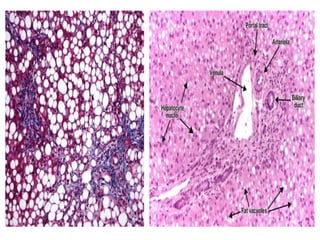

Hepatic Steatosis (Fatty Liver):

 Fatty liver is large , soft , yellow and greasy.

 Small microvesicular lipid droplets in hepatocytes.

 With chronic intake of alcohol: large, clear macrovesicular.

 Initially is centrilobular, in severe cases involve entire lobule.

 Fatty change is completely reversible if there is abstention

from alcohol intake.